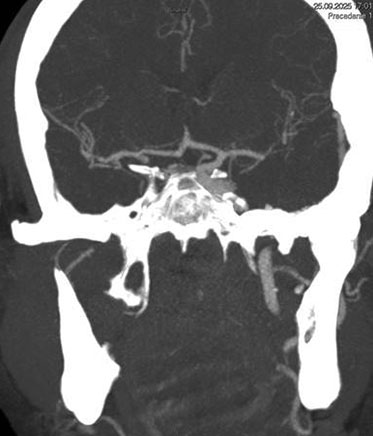

1. Occlusion of the right internal carotid artery (R-ICA intracranial segment) involving P-Com & AChA.

2. Occlusion of the right P-Com in the context of a fetal type PCA.

3. A patent apex of the right carotid artery with normal intracranial circulation elsewhere.

Two unsuccessful thrombectomy attempts were made prior to NeVa use. The NeVa pass achieved complete recanalization with no distal thromboembolism (TICI 3):

1st pass success:

TICI 3 in a single pass with NeVa 5.5 x 37mm